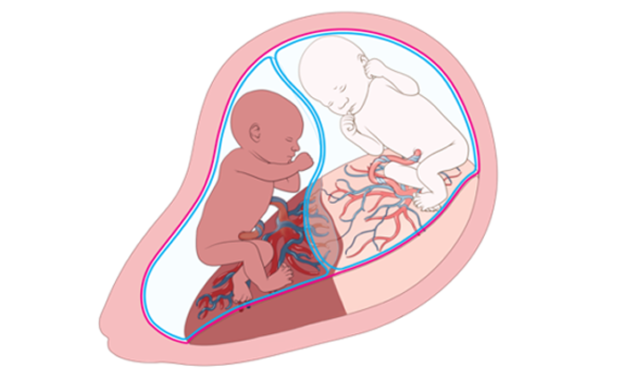

This seminar focuses on fetal diagnosis and treatment and was delivered at a virtual event titled, “More Monochorionic Pathology: TRAP, Proximate Cords and Normal Growth with Abnormal Dopplers” on January 28, 2026.